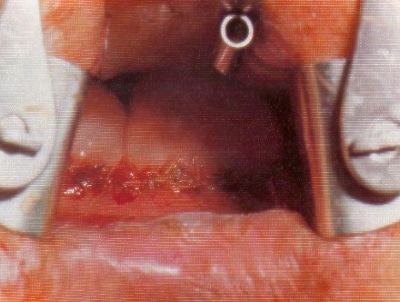

Bilddokumentation - Entfernung der Tumoren...

Bildergalerie